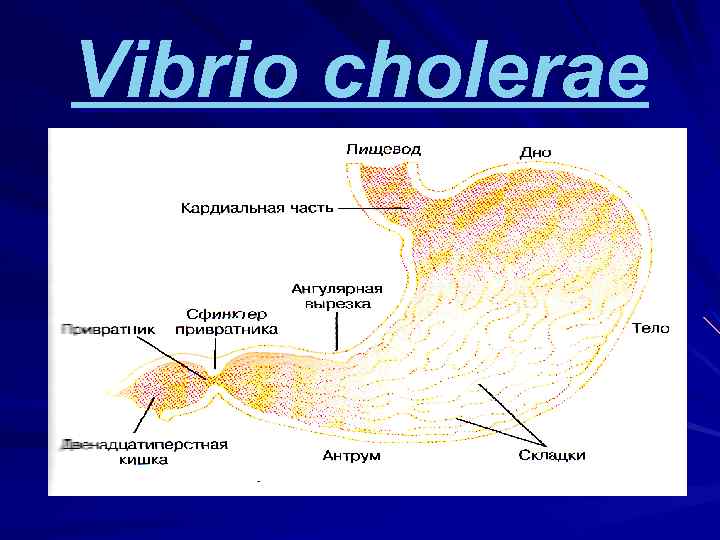

Vibrio cholerae

Vibrio cholerae